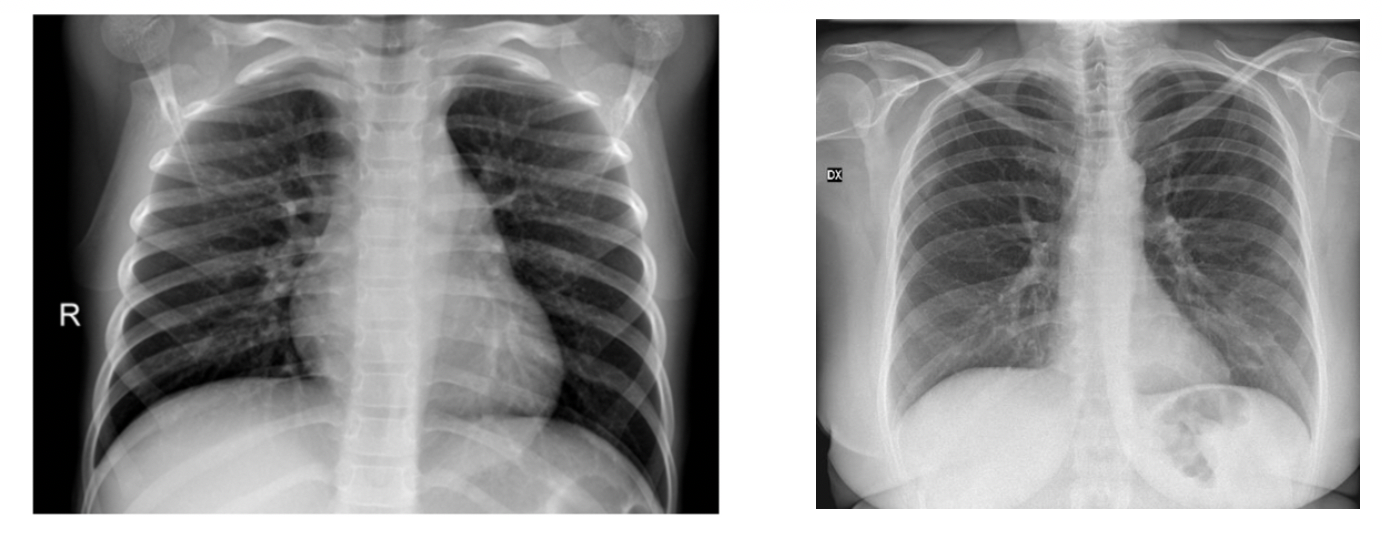

Brax contains 24,959 chest radiography exams and 40,967 images acquired in a large general brazilian hospital. Google classroom is a free blended learning platform developed by google for educational institutions that aims to simplify creating, distributing, and grading assignments. Kaggle solutions and ideas by farid rashidi.

All images have been read by trained radiologists and 14 labels were derived from brazilian portuguese reports using nlp. Unless specifically stated in the applicable dataset documentation, datasets available through the registry of open data on aws are not provided and maintained by aws. Data will be collected from public sources as well as through indirect collection from.

Content Dataset Is Organized Into 2 Folders (Train, Test) And Both Train And Test Contain 3 Subfolders (Covid19, Pneumonia, Normal).

Brax Contains 24,959 Chest Radiography Exams And 40,967 Images Acquired In A Large General Brazilian Hospital.